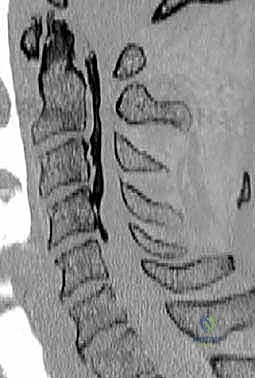

- التصوير بالرنين المغناطيسي (MRI): المعيار الذهبي لرؤية الحبل الشوكي، الأعصاب، والأقراص الغضروفية بوضوح تام، وتحديد مناطق الانضغاط.

- التصوير المقطعي المحوسب (CT Scan): ضروري جداً لتقييم البنية العظمية، التكلسات (مثل OPLL)، والكسور بدقة ثلاثية الأبعاد.